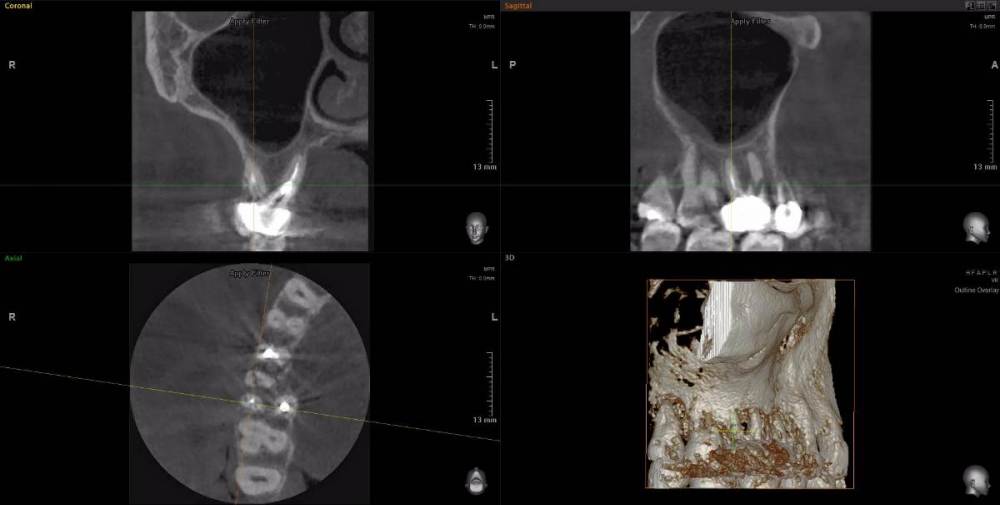

Рабин Опубликовано 18 мая, 2021 Автор Поделиться Опубликовано 18 мая, 2021 Добрый день! Сделала КТ этого зуба, как вы просили... https://cloud.mail.ru/stock/kkbze24nzBzfEqnUbdPwtsei Видите ли вы воспаление на нём и можно ли его спасти? Интересует также соседний 15 зуб. Спасибо! Ссылка на комментарий

wladdX Опубликовано 18 мая, 2021 Поделиться Опубликовано 18 мая, 2021 (изменено) Зуб 16, на мой взгляд, придётся удалить. Зуб 18 тоже Зуб 15 вроде бы и не вызывает особых восторгов, но и явного неприятия тоже. Изменено 18 мая, 2021 пользователем wladdX 2 Ссылка на комментарий

red_butler Опубликовано 20 мая, 2021 Поделиться Опубликовано 20 мая, 2021 18.05.2021 в 23:24, wladdX сказал: Зуб 16, на мой взгляд, придётся удалить. +1 Ссылка на комментарий

wladdX Опубликовано 29 мая, 2021 Поделиться Опубликовано 29 мая, 2021 18 - там приличных размеров корневая гранулёма, излечить нереально 1 Ссылка на комментарий